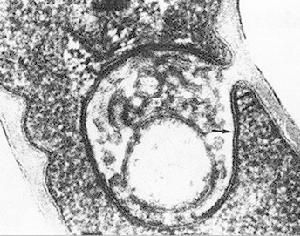

白喉桿菌尚產生一些侵襲性物質,如類似於結核桿菌的索狀因子(Cord factor),能破壞細胞的線粒體膜,導致呼吸和氧化磷酸化作用受到抑制。